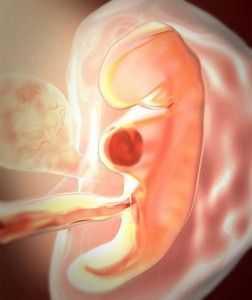

Эмбрион на 5 неделеНачинает развиваться сердечно-сосудистая система. В передней части эмбриона, в выпуклой стороне, формируется сердце и начинает биться. К концу 5 недели сердце имеет левую и правую камеру, которые сокращаются в два раза сильнее, чем у взрослого человека. К концу недели устанавливается циркуляция крови, сформируются глазные впадины, пуповина и ушные проходы. Развитие кровеносной системы ведет отсчет с клубка тканей, который в будущем будет сердцем. Далее, с центра эмбриона начнут развиваться дыхательные органы – гортань, трахея. Пищеварительная система пока слабо выражена.

Появятся зачатки рук и ног. Произойдёт закладка важных органов для ребёнка: печени, почек, органов пищеварения и выделительных органов. Форма эмбриона напоминает грушу и при детальном рассмотрении можно увидеть различные части тела. Положение плода напоминает букву С, в ней он пробудет ближайшие месяцы. В эту неделю активно расширяется нервная трубка, она будет формировать головной мозг и нервную систему. За 5 недель беременности успевает развиться специальный так называемый желточный мешок с жидкостью внутри. Его функцией на данном этапе является формирование кровяных клеток.

Эмбрион еще очень маленький: всего около 2 мм в длину, а вес его меньше грамма. Несмотря на размеры, плод уже немного подтягивает будущие ножки к голове и становится похожим на букву С.

Пока еще малыш совсем не похож на ребенка, однако у него уже есть зачатки ручек и ножек. На сроке в пять недель они практически незаметны и больше похожи на плавники. На голове ребенка формируются отверстия, в которых будут располагаться глаза и уши.

Беременность 5-6 недель характеризуется активным развитием эмбриона. На этом сроке эмбрион имеет форму небольшой дуги длиной около 3-5 мм и весом не более 3,5 г. В силуэте эмбриона уже можно заметить зачатки будущих рук и ног, позвоночника и головы, а также сердца, которое на 5 неделе беременности выглядит в форме сгустка темного цвета. Поразительно, но именно на этом раннем сроке сердечко уже стучит!

На 5 неделе беременности происходит одно очень важное событие: тело зародыша обособляется от внезародышевых частей. Оно уже имеет свою пространственную ориентацию: передний конец (будущая голова) и задний конец (будущий таз и нижние конечности). На 5 неделе беременности появляются зачатки всех основных функциональных систем и органов человеческого организма.

В центре эмбриона есть клубок ткани – начинается закладка сердца (вместе с закладкой верхних дыхательных путей гортани и трахеи). Постепенно начинают формироваться и кровеносные сосуды. Появляются зачатки печени и поджелудочной железы. На 5 неделе беременности зародыш изогнут в форме буквы «С». Вдоль нервной трубки формируются сегменты ткани (сомиты). Из них в дальнейшем возникает мышечная ткань и другие тканевые структуры. На 5 неделе беременности также происходит частичное смыкание (закрытие) нервной трубки (пока еще только в средних ее отделах). Нервная трубка это прообраз центральной нервной системы, поэтому ее своевременное закрытие является событием немалой важности.Большую роль в этом событии играет принимаемаятобой фолиевая кислота (в составе мультивитаминов или отдельно).